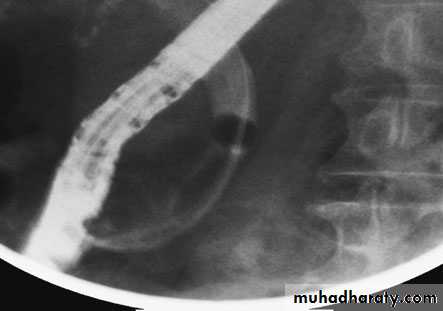

Endoscopic retrograde cholangiopancreatography: thepatient presented with jaundice 4 days after laparoscopic cholecystectomy.The bile duct contained multiple stones